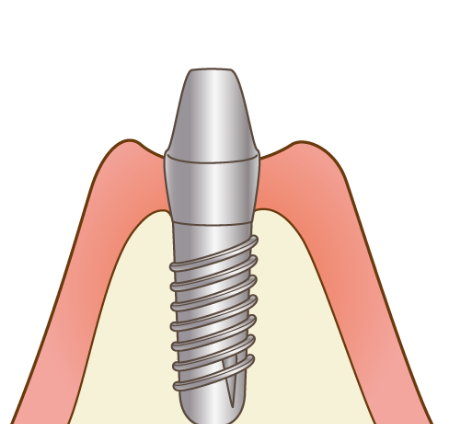

当院のインプラントは、40年以上の歴史があるノーベルバイオケア社(スイス)を使用しており、骨との親和性に優れる「純チタン」の表面に「タイユナイト」と呼ばれる表面加工が施されており、周囲の骨形成が促進されると言われています。